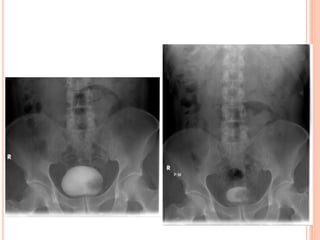

VOIDING

CYSTOURETHROGRAPHY

VCUG is commonly performed in children

with prenatally diagnosed hydronephrosis,

urinary tract infections, and voiding

abnormalities.

The procedure should include assessment

of the spine and pelvis; masses or opaque

calculi; bladder capacity, contour, and

emptying capability; presence and grade of

reflux; and urethral appearance.

BLADDER FILLING

Early Filling

Several seconds after the contrast

material begins to flow, the minimally

filled bladder is imaged in the AP view.

A ureterocele or bladder tumor that is

well seen during early filling may

become obscured as more contrast

material enters the bladder

INTERMEDIATE FILLING

Vesicoureteral reflux can be

seen on oblique radiographs

obtained just before voiding

and can be graded after

voiding with the International

Reflux System.

PREVOIDING IMAGING

If reflux is observed during late bladder

filling, the ipsilateral renal fossa may be

imaged in the anteroposterior projection

prior to voiding.

IMAGING DURING VOIDING

Bladder capacity={Age(ys)+2}x30.

A smaller than expected voiding volume

may also indicate a neurologic abnormality

(spastic bladder) or active bladder

infection.

POSTVOIDING IMAGING

At the conclusion of voiding, each

renal fossa should be imaged. Still

images may demonstrate reflux that is

not appreciated at fluoroscopy as well

as other anomalies or abnormalities.